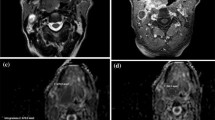

The ROIs were placed by a radiologist (3 years’ experience) under the supervision of another radiologist (21 years’ experience). The first 24 participants were also independently analysed by a further radiologist (5 years’ experience) to assess for inter-observer agreement. ROIs were placed individually within the primary tumour and/or the largest pathological lymph node (Figs. 1, 2) using OsiriX v8.0.2, open-source Mac-based medical image processing software. ROIs were placed on the pre-treatment, 6-week (ADCmean6) and 12-week (ADCmean12) post-treatment MRI studies using the DWI b = 800 s/mm2 map, but with access to other MRI sequences. When a focus of increased DWI signal was not evident on post-treatment images, a standardised 6 mm diameter ROI was placed at its original location. An ADC map was generated from the b 100 and b 800 s/mm2 images. A ROI was also placed within the cervical spinal cord on the ADC map as a reference.

A HPV-positive participant with a left palatine tonsillar tumour. A T1w post gadolinium axial image pre-treatment demonstrates the left palatine tonsillar tumour (arrow). b b = 800 s/mm2 map from DW-MRI pre-treatment indicating the primary tumour ROI as the increased DWI signal. C T1w post gadolinium axial image at 12 weeks post-treatment demonstrates the primary tumour to be of reduced size (arrow). b b = 800 s/mm2 map from DW-MRI at 12 weeks post-treatment indicating the primary tumour standardised 6 mm ROI since there is no increased DWI signal relative to adjacent oropharyngeal tissue. e 18F-FDG PET-CT study at 12 weeks post-treatment demonstrating the 6 mm VOI at the primary tumour. Since there is no 18F-FDG uptake to target, it is placed with guidance from the MRI study

A 6 mm diameter volume of interest (VOI) was placed by a radiologist (3 years’ experience), under the supervision of another radiologist (16 years’ experience). VOIs were placed at the site of most intense FDG uptake within either the primary lesion and/or the largest lymph node, which were matched to the ROI placed for the MRI analysis (Figs. 1, 2). If there was reduced uptake on the post-treatment images relative to background, a 6 mm VOI was placed at the same site as the post-treatment MRI ROI. If necrosis was identified within a lesion, the area of necrosis was excluded. The SUVmax was calculated with semi-automated software on a Hermes workstation (Hermes Gold 3, Stockholm).